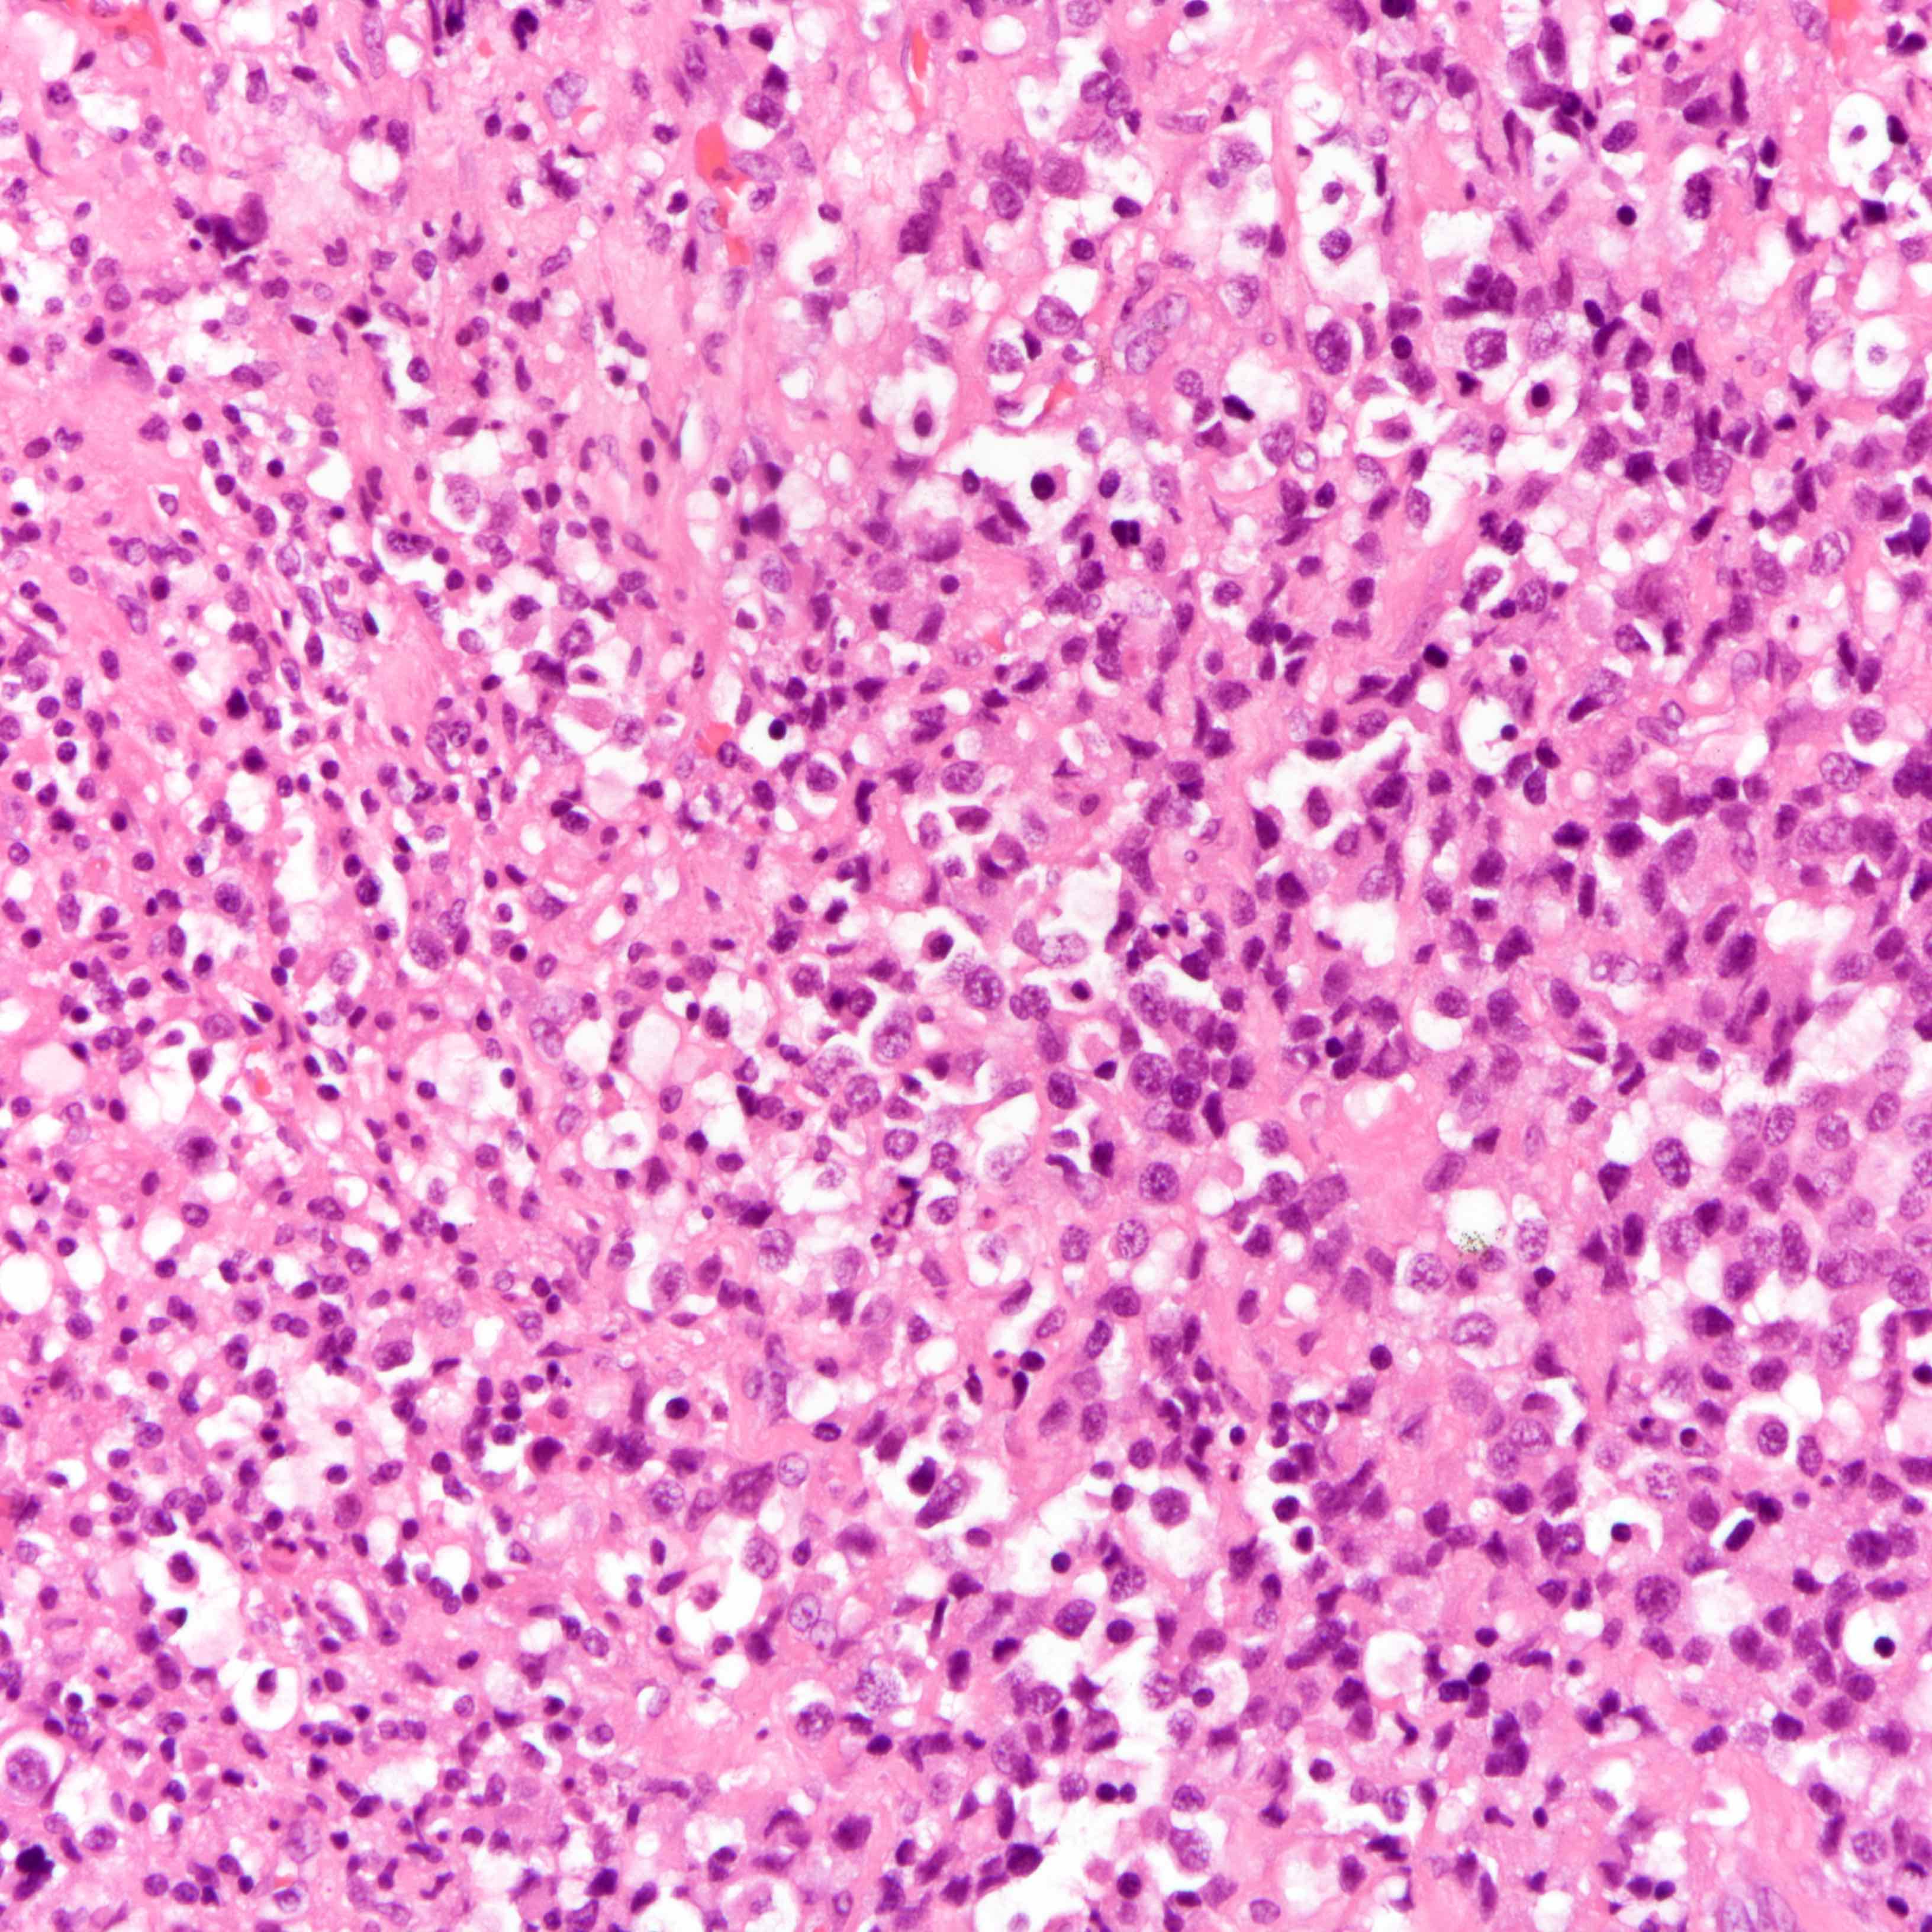

Microscopic (histologic) description

- Incomplete response / residual disease: evidence of tumor response but residual tumor cells are present

- No response: treatment associated changes are not seen histologically

- Histologic evidence of tumor response includes fibrosis, hyalinization, lymphohistiocytic infiltration, hemosiderin laden macrophages, giant cell formation and vascular proliferation

- These histologic features are indicative of the tumor bed

- Patterns observed in partial response includes concentric tumor shrinkage, reduction in tumor cellularity and scattered multifocal tumor deposits (Mod Pathol 2015;28:1185)

- Tumor cells show degenerative changes including nuclear and cytoplasmic vacuolation, karyorrhexis, karyolysis and pyknosis (Int J Appl Basic Med Res 2012;2:111)

Microscopic (histologic) images

Contributed by Joshua J.X. Li, M.B.Ch.B., Gary M. Tse, M.B.B.S. and Emily S. Reisenbichler, M.D.